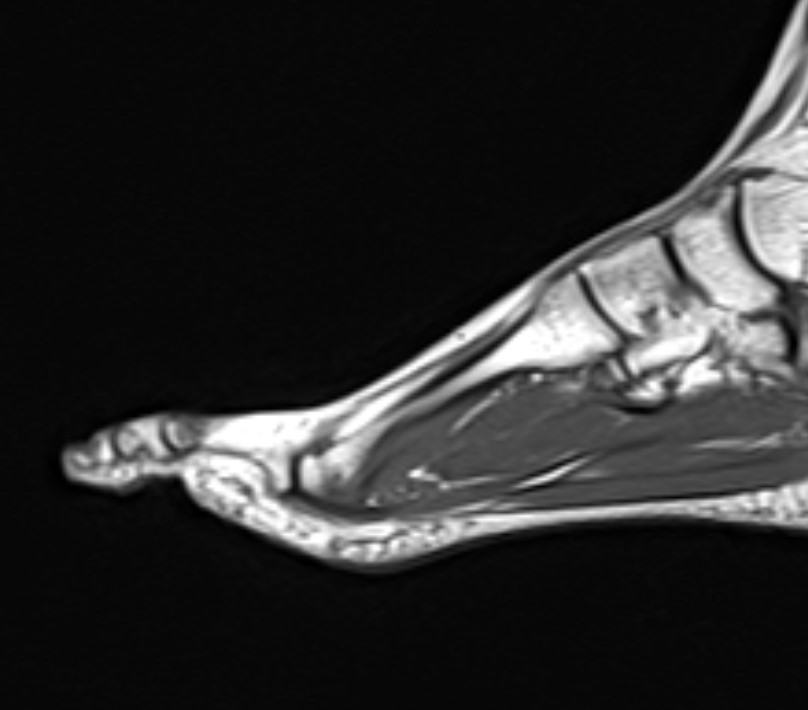

В клинике «Доступная медицина» данное исследование проводится на современном высокопольном магнитно-резонансном томографе экспертного класса TOSHIBA VANTAGE TITAN 1,5 Тесла. Напряженность магнитного поля 1,5 Тесла обеспечивает высокую разрешающую способность аппарата, что позволяет выявлять минимальные изменения в тканях и диагностировать заболевания на начальной стадии.

В большинстве случаев проводится стандартная магнитно-резонансная томография стопы без использования контраста, однако в некоторых случаях требуется контрастное усиление для детализации патологических очагов. Для этого применяется контрастное вещество на основе гадолиния (элемент, относящийся к редкоземельным металлам), которое полностью выводится из организма в течение суток преимущественно почками.